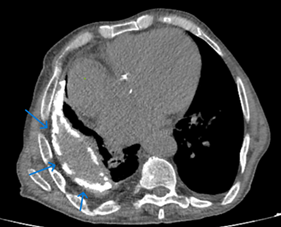

The duration of his anti-tuberculosis treatment and the specific medications he got remain unknown. He has a smoking history of 20 packs per year, has been smoke-free for 35 years, and abstains from alcohol consumption. He had hypertension and heart failure, but the patient had no history of regular drug use. He has been having frequent coughs, phlegm and shortness of breath for about 20 years. He was given oral antibiotic treatments, but when his complaints started to regress, he did not go for follow-up examinations. He used oral antibiotics 4 times in the last year, and hospitalization was recommended once, but the patient did not accept it. Looking at the patient's retrospective examinations, pleural thickening, areas containing fluid density, and calcifications were observed in the right hemithorax in the Thorax CT scans taken in 2010 and 2022 (Figures 1 & 2). In the CT scan of the patient taken in January 2024, approximately 3,5 cm was observed on the right hemithorax, which could be evaluated in favor of pleurisy sequelae (Figures 3 & 4). Sputum analysis for three Acid-resistant bacilli tests was negative. There is no elevated sedimentation, CRP, or leukocytosis.

Figure 2 Mediastinal window of April 2022 thorax CT, the lesion structure remained stable and became more calcified.